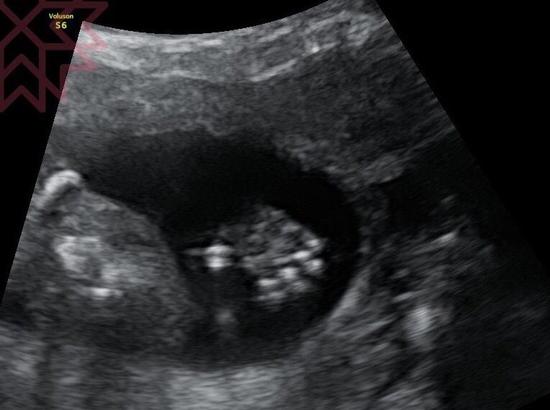

伊能静晒二胎产检B超照 称手脚都看得到

伊能静晒二胎产检B超照。